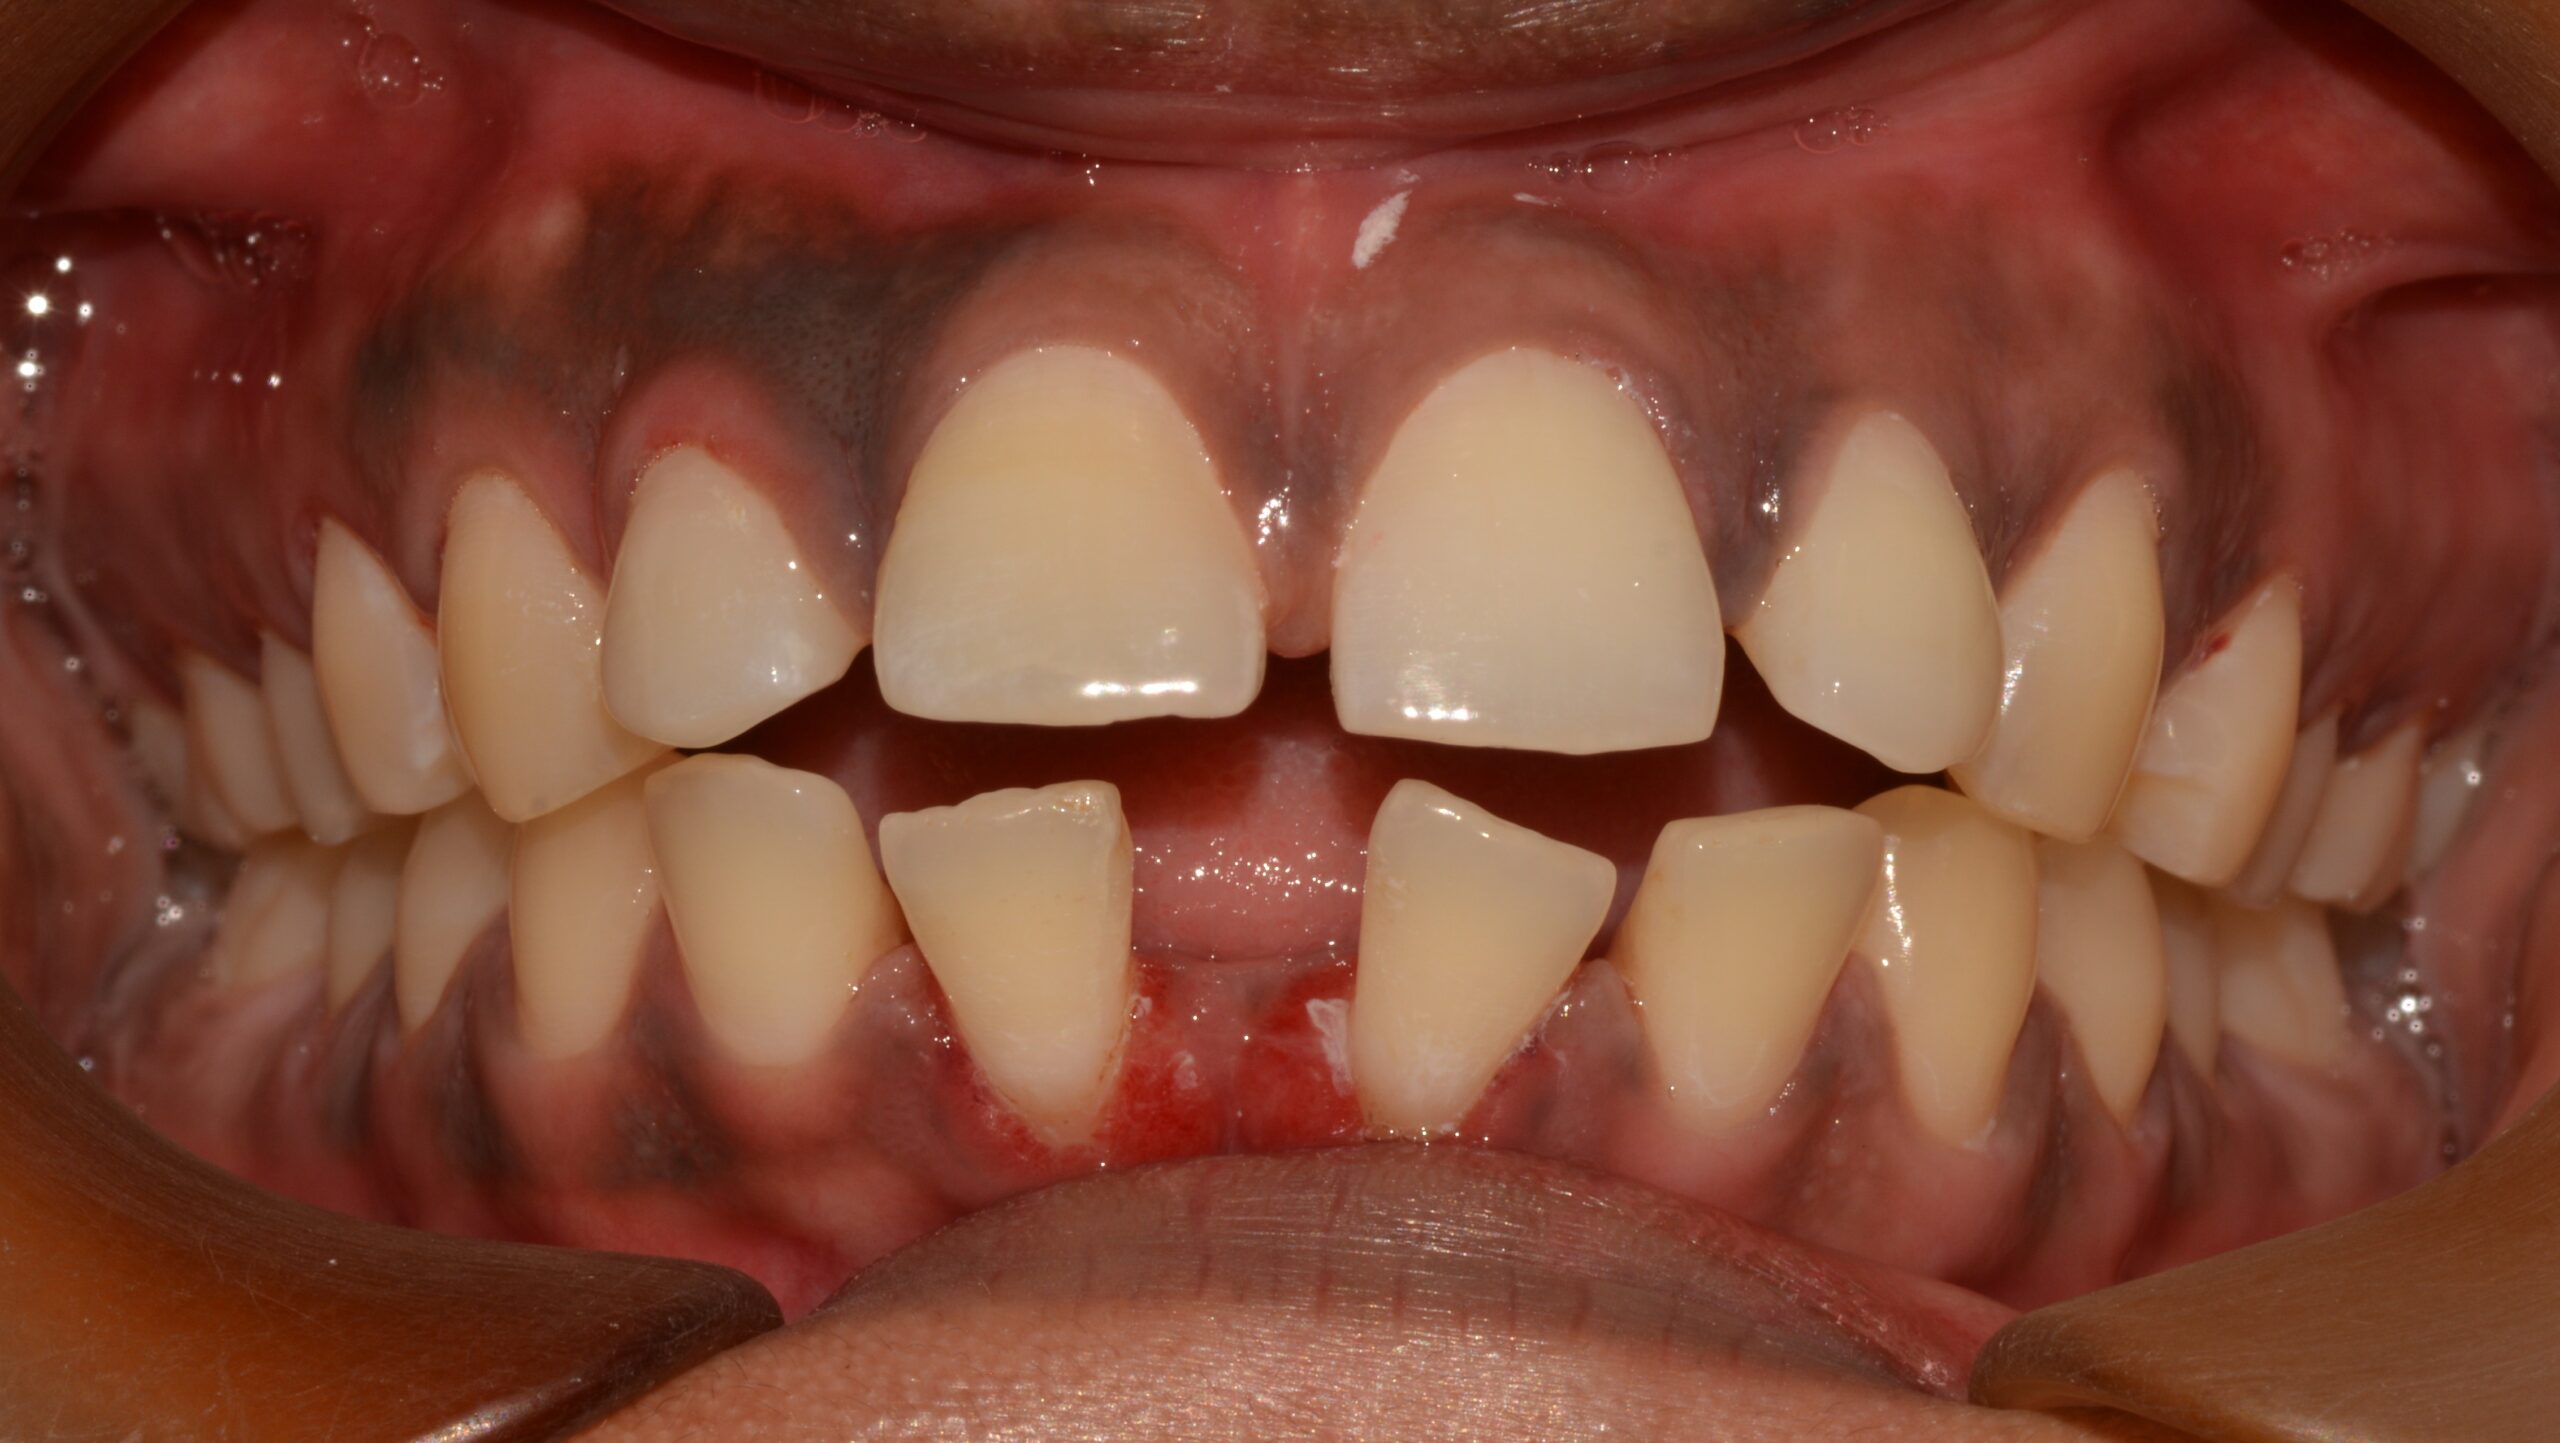

The patient had large gaps between the teeth, which were slowly being pushed forward by the tongue. This made the teeth loose and was further complicated by gum issues due to not visiting the dentist regularly for cleaning and check-ups.

If left untreated, the patient could have suffered tooth loss, especially in the front tooth region, leading to an altered smile at a very young age.

The gaps occurred because there was more space in the jaws compared to the smaller-sized teeth. It could also have been caused by the habit of pushing the tongue forward onto the front teeth, known as tongue thrust.

Before